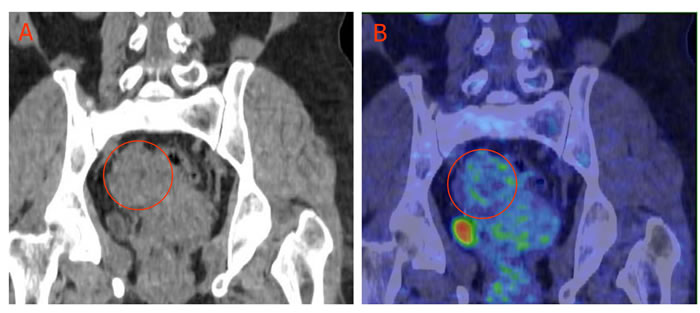

During the past decades, the wide use of 18F-FDG PET and PET/CT in cancer detection demonstrated that some untreated malignant lesions (cancer type dependent) may have negative or low 18F-FDG uptake [15] (Figure 2). Ours and others preclinical research demonstrated a close ties between tumor 18F-FDG activity and its hypoxia. Thus, well oxygenated malignant tumors may be non-18F-FDG-avid, a combination of early phase perfusion and balance phase metabolism 18F-FDG PET imaging may give a more accurate estimation of viable cancer cell burden.

Figure 2: Low 18F-FDG uptake in ovary granulosa cell tumor. A 54-yr-old female with pathologically confirmed granulosa cell tumor of the right ovary (circled), 18F-FDG accumulation in the tumor is low. A: CT imaging; B: 18F-FDG PET/CT overlay obtained 60 min after 5 mCi (185MBq) 18F-FDG intravenous injection.